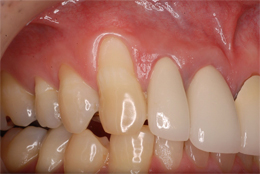

結合組織による根面被覆症例

-

- 主訴

- 右上3番がしみる

- 治療内容

- 右上3の歯頸部過度なブラッシングにより歯肉退縮したもので、右上口蓋より結合組織を採取し、歯根露出部に移植

- 治療費用

- CTG:60,000円(税別)

- 治療期間

- 術後3ヶ月の状態